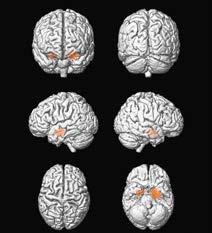

Eine sehr wahrscheinliche Erklärung für das häufige Auftreten von psychischen Wechseljahrbeschwerden sind die natürlichen Schwankungen des weiblichen Hormonspiegels in dieser Zeit durch die abnehmende Aktivität der Eierstöcke. Diese Hormonschwankungen wirken sich auch auf Vorgänge im zentralen Nervensystem im Gehirn aus. Genauer gesagt wirken sie auf jene Schaltkreise, die auch für die Entstehung von Depressionen verantwortlich sind. Das führt auch dazu, dass sich depressive Verstimmungen, die schon vor den Wechseljahren aufgetreten sind, in dieser Phase wieder merklich verschlimmern können.

Beteiligt sind auf jeden Fall Botenstoffe im Gehirn, die bestimmte Nervenzellen aktivieren. Die Konzentration dieser Botenstoffe im Gehirn wird unter anderem auch durch Sexualhormone beeinflusst. Schwankende Progesteron- und Östrogenspiegel in den Wechseljahren können daher auf diese Weise den Gemütszustand aus der Balance bringen.

Zu den geschlechtsunspezifischen Funktionen von Estradiol gehören die Beeinflussung des Knochenwachstums und der Knochendichte, der Erhalt der Knochenmasse sowie Effekte auf Durchblutung und Blutgerinnung. Daneben nimmt das Hormon auch Einfluss auf die Beschaffenheit der Haut sowie den Fettstoffwechsel. Im Gehirn fördert es die Ausschüttung von endogenen Opiaten wie Dopamin und Katecholamin. Hiermit beeinflusst Estradiol unter anderem die Stimmungslage.